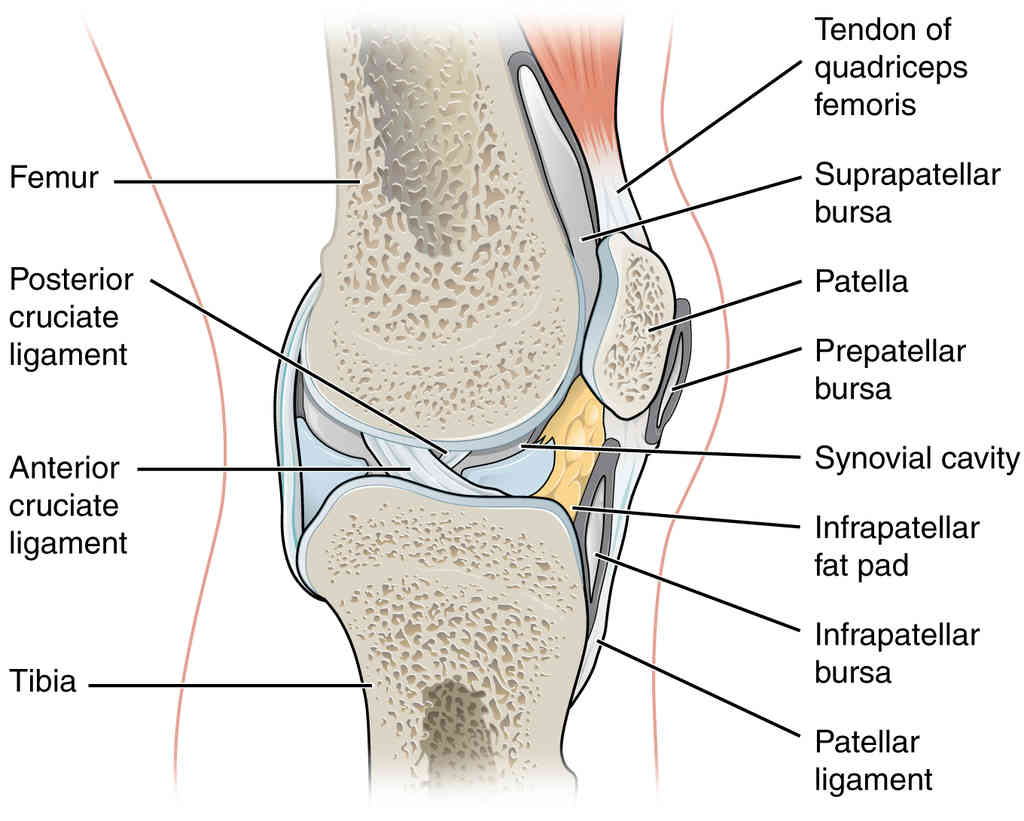

This page is under construction. For now, it is just a resource of the images found in the OpenStax Anatomy and Physiology Handbook. It wil slowly change into a revision tool. Each slide has a number. Use this to refer to the slide. When completed, it will have an unlabelled section, with labelled slides in parallel. On the unlabelled slides, write your answer and use the labelled slide to assess yourself. Keep track by also noting the number on each slide. Improvement at each attempt is important, more so than full marks on a first attempt.